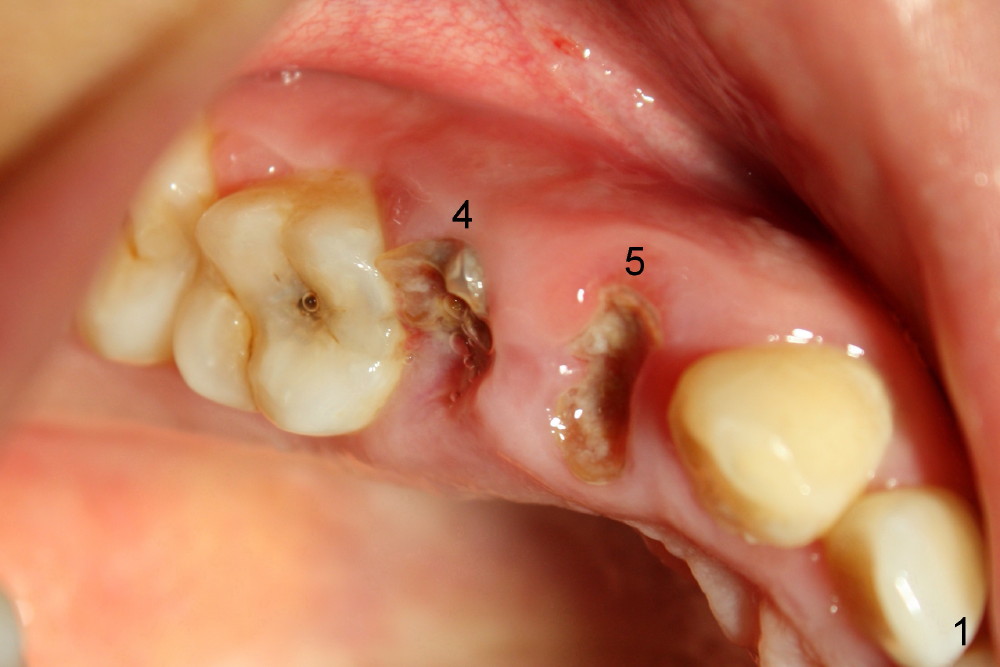

Twenty-seven-year-old Mickey has short clinical crowns in the maxilla (Fig.1). Two of the premolars (#4,5) have severe caries. When immediate implants were placed (Fig.2: I), there is no room to install abutments, probably due to the supraeruption of the opposing teeth (Fig.2 arrows). Three mini-implants (2 buccal (Fig.2), one lingual (Fig.3 <) were placed for intrusion.